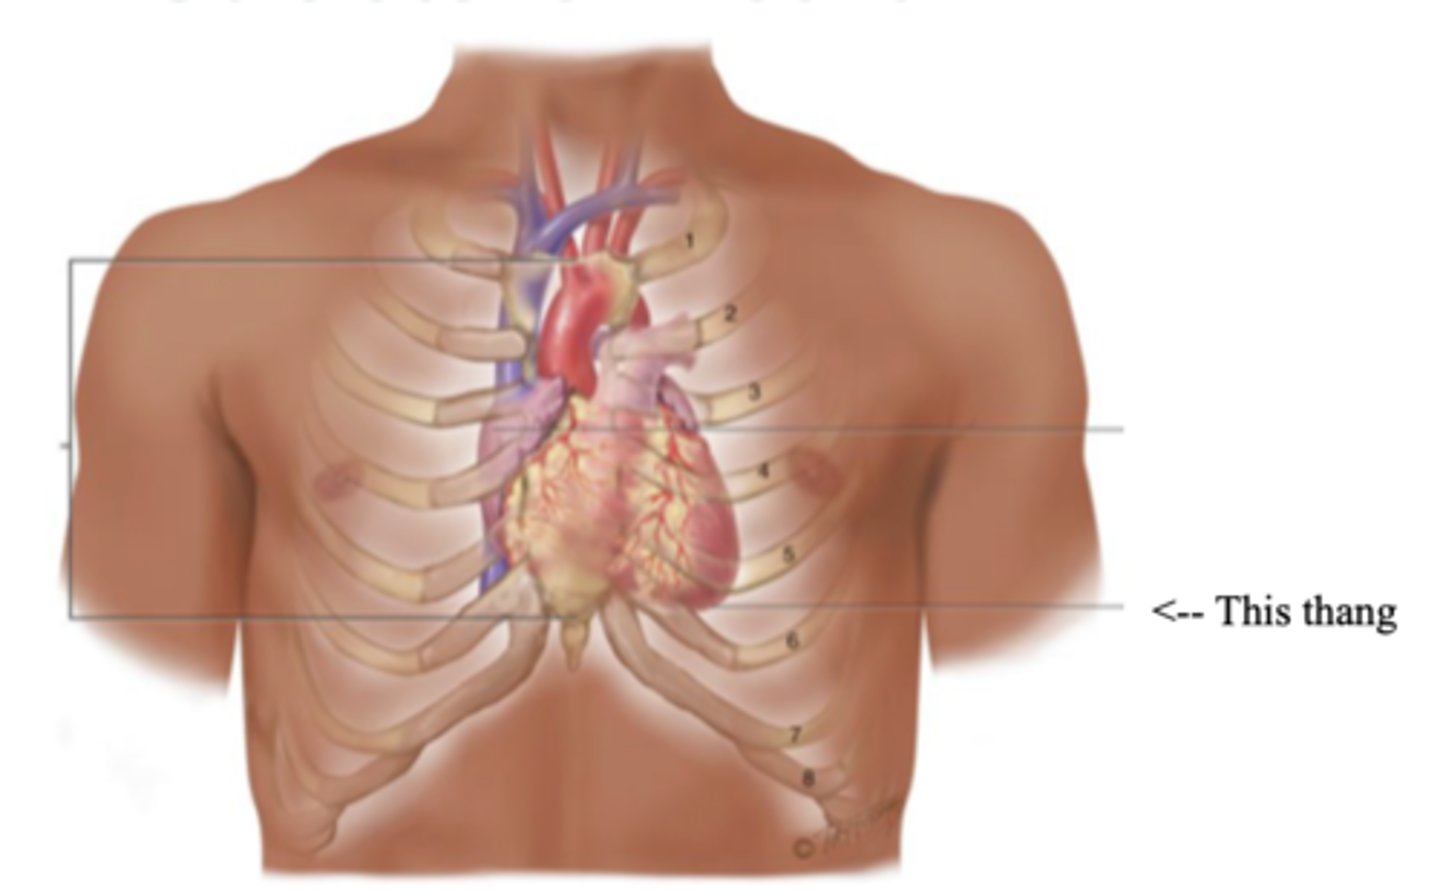

Precordium

The area on the anterior chest overlying the heart and great vessels

Mediastinum

The space located between the lungs where the heart is found

Apex (Heart)

The bottom part of the heart which points down to the left

Base (Heart)

The top broader part of the heart

Right Cardiac Border

An area formed by the right atrium

Left Cardiac Border

An area formed by the left ventricle

Anatomy of the Heart